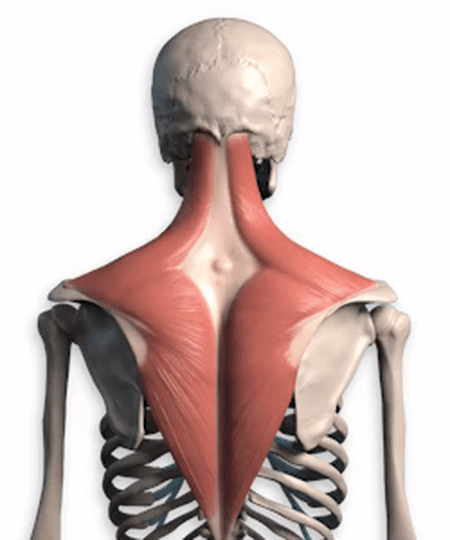

Bei Schmerzen in diesem Bereich ist es wichtig, zunächst herauszufindenDer genaue Ort des SchmerzesHeute wird Dr. Kong mit Ihnen über dieses Thema sprechen. Schmerzen im Bereich des Schulterblatts, wie auf dem folgenden Bild zu sehen:

In der Abbildung.Beschwerden in und um den rot eingekreisten Bereich werden als Schmerzen in der Skapularregion bezeichnet.. So ist es möglich, zurück zu denken, ist es möglich, dass Sie oft Schmerzen in einem dieser Orte irgendwo Ort Ort? Die relative Ursache des SchmerzesDafür gibt es viele Gründe, wie z. B. Bandscheibenvorfälle und Fehlhaltungen.Als Nächstes wollen wir uns speziell mit den Bereichen und Ursachen befassen, die häufig Schmerzen verursachen.

Viele meiner Freunde denken, dassDer Nacken ist der Nacken, die Schultern sind die Schultern, der Rücken ist der Rückendass die drei nicht viel miteinander zu tun haben, in Wirklichkeit ist diese Idee voreingenommen, von den Medizinstudenten, wir sollten die颈, Schulter, RückenBetrachten Sie ihn als einen einzigen Muskel und geben Sie eine kurze Analyse dieses Muskels, nämlich desTrapezmuskel (des oberen Rückens und des Halses)。

Wenn Sie genau hinschauen, sehen SieDieser Trapezius.einschließen.Schädelbasis, Nacken, Schultern und RückenDie Trapezmuskeln auf beiden Seiten sind eng miteinander verbunden und bilden zusammen eine rhomboide Struktur, die für die Aufrechterhaltung des Gleichgewichts wichtig ist.Stabilisierung des RückensSie spielt eine sehr wichtige Rolle bei der Bewältigung zahlreicher Tätigkeiten im Nacken-, Schulter- und Rückenbereich und wird in der Medizin alsDer Trapeziusmuskel ist in ein oberes, mittleres und unteres Bündel unterteilt, und die verschiedenen Teile der Kontraktion führen unterschiedliche Bewegungen aus。

Das ist nur ein Muskel, es gibt noch viele weitere im Nacken, in den Schultern und im Rücken.Fleischdie alle miteinander verbunden sind, einschließlichFaszien unter der HautEs ist auch alles ein und dasselbe, wir können den Nacken, die Schultern und den Rücken nicht trennen, ich glaube, das sollten wir verstehen.